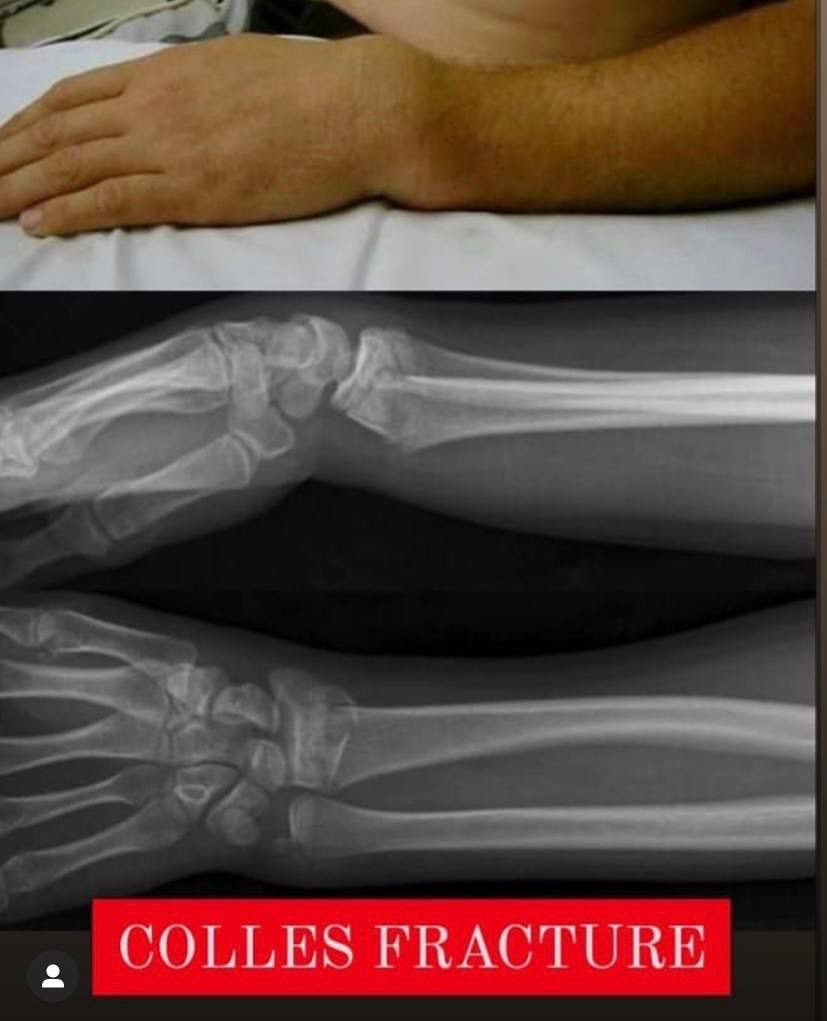

Colles fracture

Fracture

Deformity

Colles

Dinner

Forks